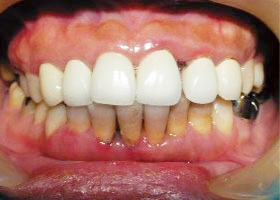

病患: 47歲,女性。

- 上顎前牙為假牙套,牙縫過大,容易塞食物,且略微暴牙,導致講話有點漏風;假牙顏色過白,病患覺得不甚美觀。

- 上下顎顏色色差過大,困擾已久。

上顎六顆前牙有牙周病,且假牙密合度不佳;下顎有明顯四環黴素染色,造成上下顎色差及美觀問題;且 確實有暴牙。

1. 術前口內正面照、局部X光片。

2. 上顎明顯暴牙、下顎參差不齊。